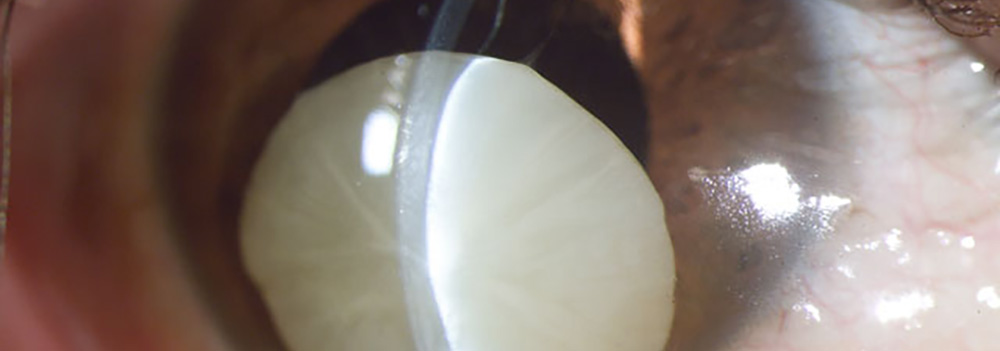

Luxación de Cristalino, Catarata. Fotografía, Instituto Barraquer de América